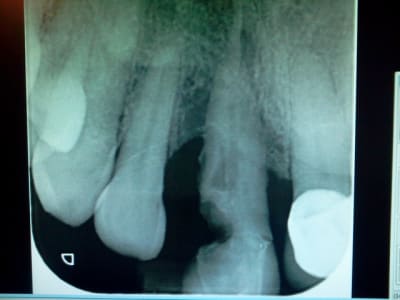

Une radio serait interessante.

Merci pour vos réponse j essaie de poster une rx demain.

Voilà la radio.